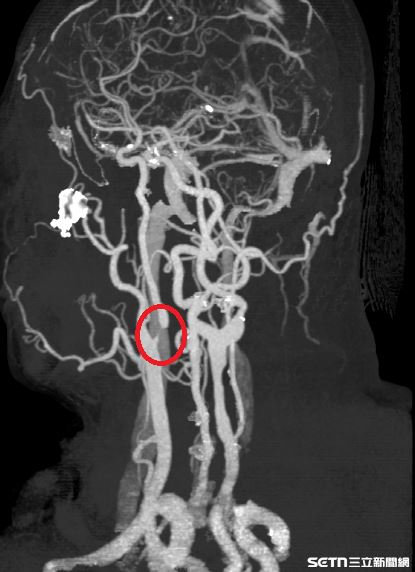

50歲的林先生近日常不時感到頭暈目眩,且左邊的手腳也老是感覺麻麻的,本不以為意,但出現的頻率越來越頻繁,他驚覺不太對勁,便前往衛生福利部南投醫院看診。神經內科鄭耕兆醫師初步安排林先生進行電腦斷層檢查,雖沒有發現明顯中風跡象,但基於臨床警覺,進一步安排頸動脈超音波檢查,結果發現內頸動脈已有狹窄情形,隨即收治住院觀察,並轉介神經外科陳奕安醫師。

談及林先生的狀況,神經外科陳奕安醫師指出,頸動脈狹窄是導致缺血性中風的重要原因之一,早期症狀常不明顯,或僅表現出短暫性頭暈、單側肢體麻木、甚至視力短暫變黑(黑矇)等,所以容易被民眾忽視。陳醫師進一步補充道,一旦血流受阻,可能造成腦部長期缺血,進而增加中風風險。

針對這類的病人,以林先生為例,他在接受內頸動脈血管成形術(氣球擴張合併支架置放),手術相當順利且成功改善腦部血流,術後也恢復得很好,已出院返家。但陳奕安醫師特別提醒,患者術後需長期服用抗血小板的藥物,以預防血管再次阻塞,並須配合定期追蹤檢查,確保血管通暢。